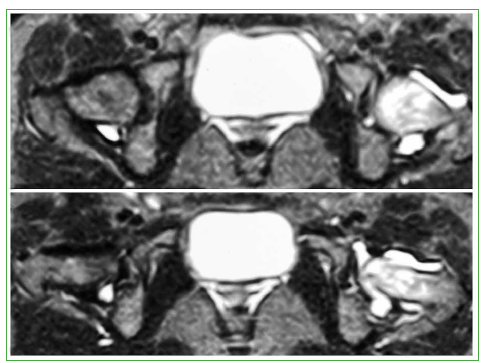

La paciente llega a la consulta con radiografías previas (no se muestran), imágenes de RM y TC tomadas en otra institución, y diagnóstico de sinovitis transitoria. Las imágenes de RM de ambas caderas (21 de octubre de 2019), corte axial en secuencias potenciadas en T2 muestran edema óseo en la cabeza y el cuello del fémur izquierdo, asociado a un aumento del líquido articular (Figura 1).

Figura 1.

Resonancia magnética de caderas, corte axial en secuencias potenciadas en T2. Se observa edema óseo en la cabeza y el cuello del fémur izquierdo, asociado a un aumento del líquido articular.